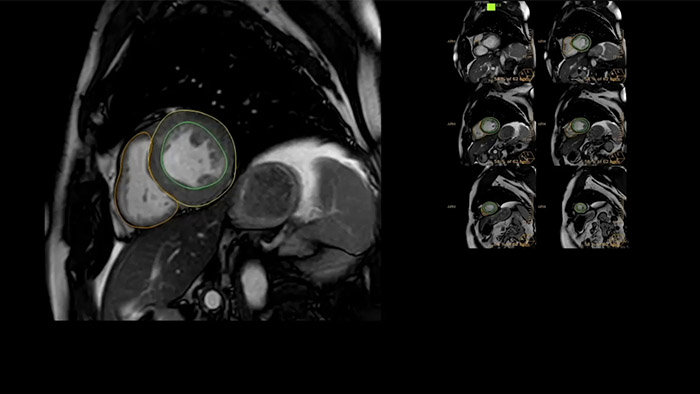

IntelliSpace Portal offers a Comprehensive Cardiac MRI Suite, providing dedicated workflows for functional analysis, viability, LGE, cardiac mapping assessment and RV/LV functional analysis in less than 5 min. per case1.

Diagnostic and prognostic utility of cardiac MR is increasing. Assess the anatomy and function of the heart using cine acquisitions, acquire information about perfusion and viability of the cardiac tissue, visualise potential edema with black blood sequence, access and even quantify tissue characterisation with CardiacQuant.